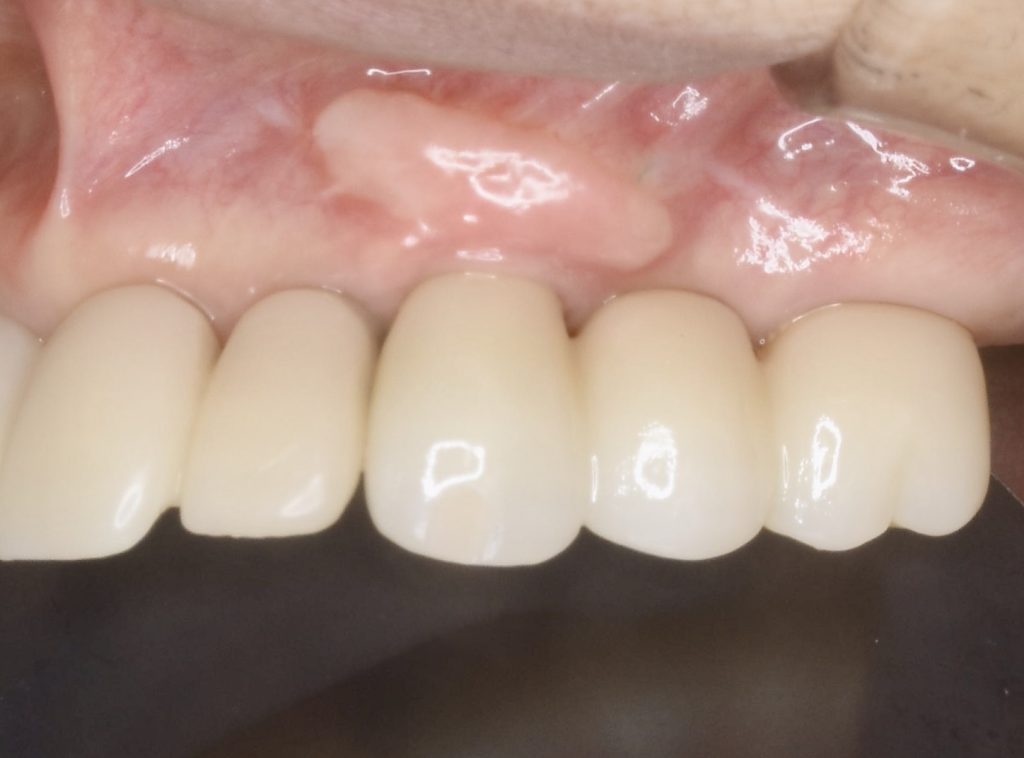

下記の症例は骨幅が薄く、このままでは長期的に安定したインプラント治療が不可能だったので、抜歯と同時に骨造成(GBR)を行い、その後歯肉移植(FGG)を行い、術後安定した経過を辿るよう配慮致しました。